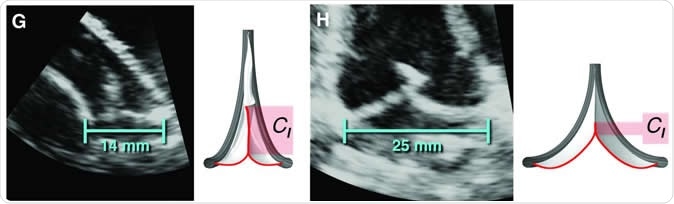

The valve replacement expanding to accommodate different lengths in implanted sheep. This material relates to a paper that appeared in the Feb. 19, 2020, issue of Science Translational Medicine, published by AAAS. The paper, by S.C. Hofferberth at Boston Children's Hospital in Boston, MA; and colleagues was titled, "A geometrically adaptable heart valve replacement." Image Credit: S.C. Hofferberth et al., Science Translational Medicine (2020)